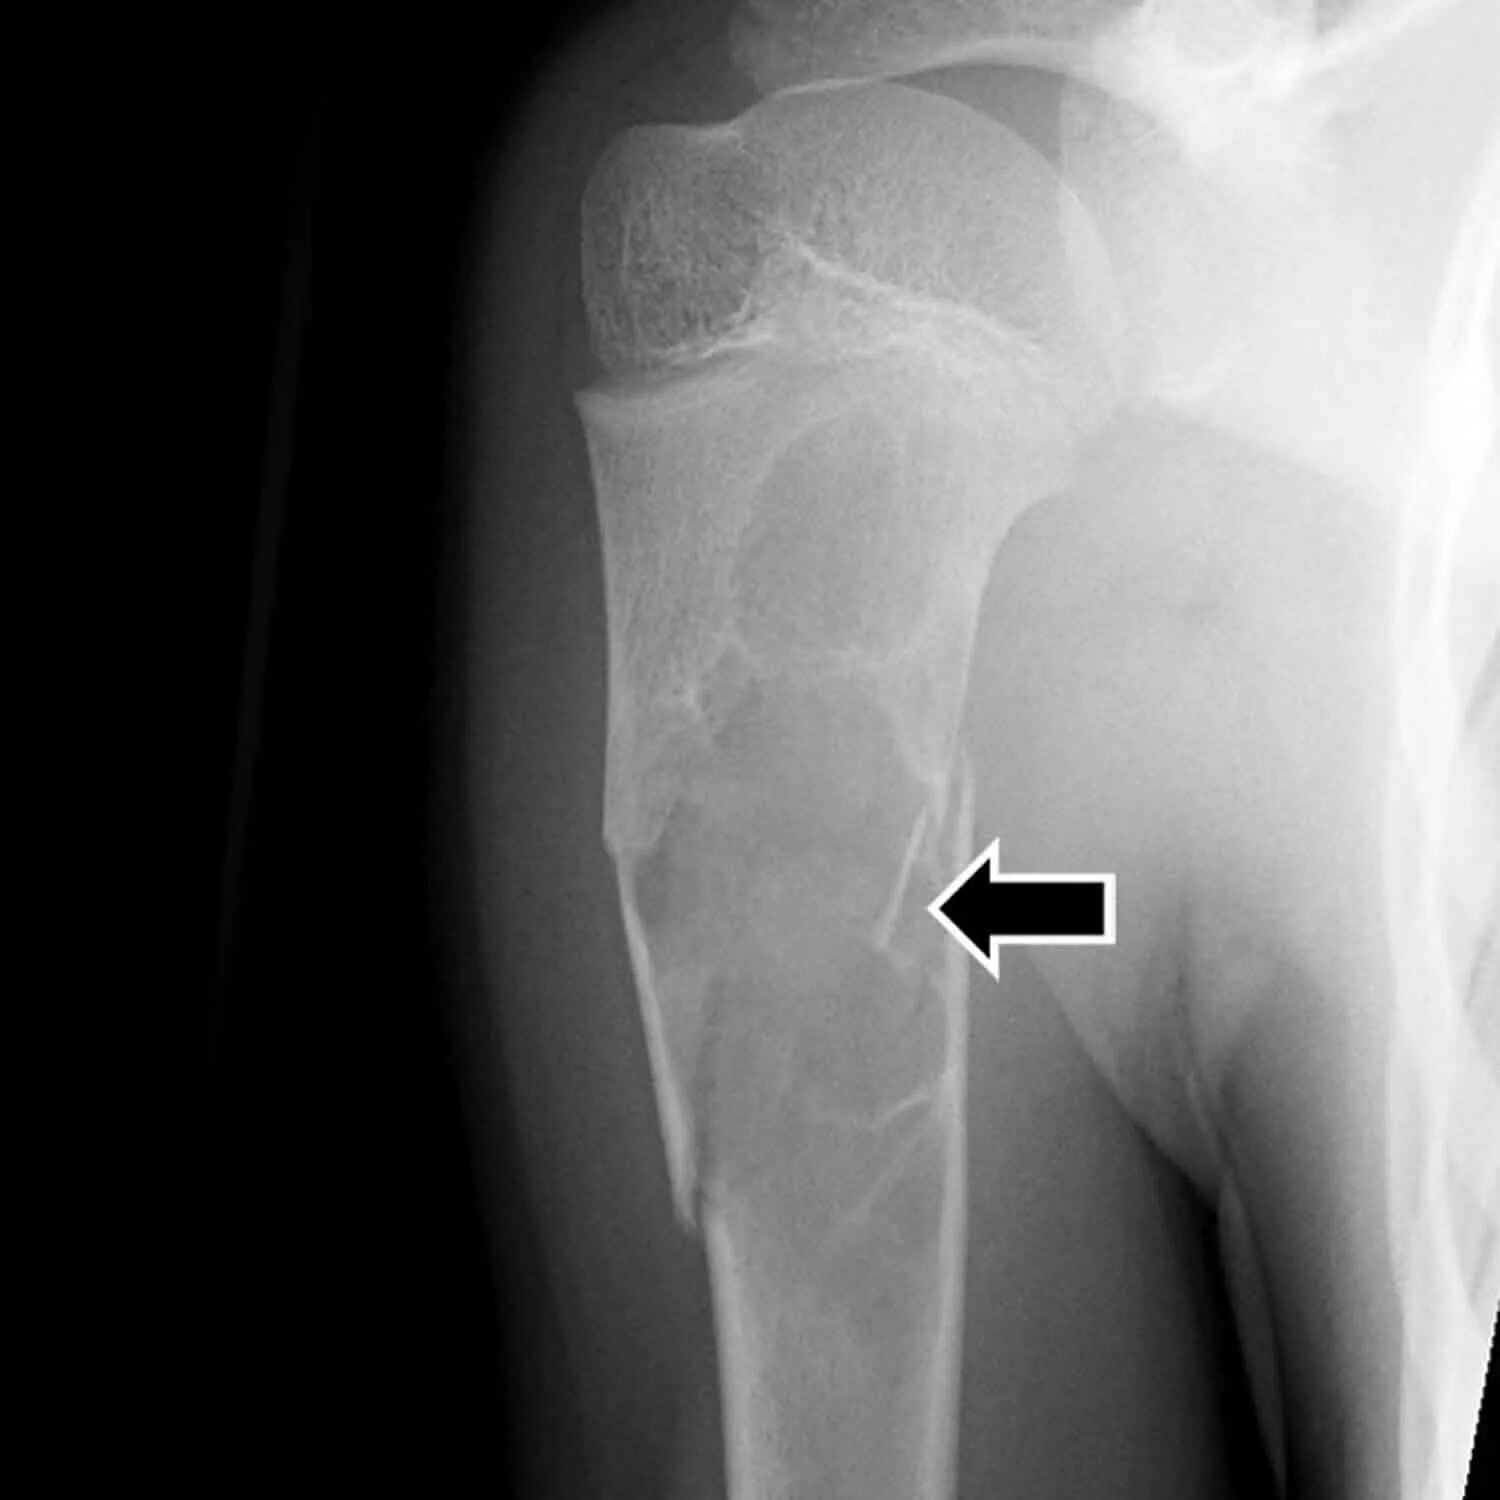

Патологический перелом бедра